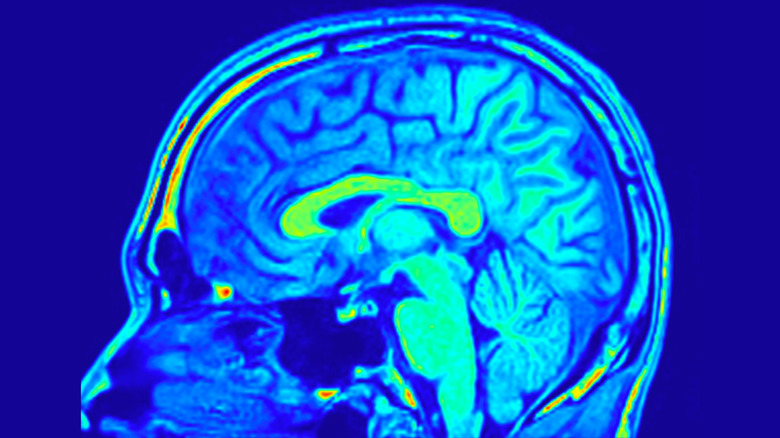

Peut-être étonnamment, l'écriture à la main tombe également dans cette catégorie, et des études montrent que différents réseaux de neurones sont impliqués lorsque nous écrivons à la main par rapport à la frappe. Lorsque des électrodes ont été attachées aux participants qui ont écrit en cursive, et d'autres qui ont tapé sur un clavier, comme prévu, une activité cérébrale accrue a été détectée dans les zones liées au contrôle moteur dans les deux ensembles de participants. Cependant, chez ceux qui ont écrit à la main, les bandes alpha et thêta ont également vu une augmentation de l'activité. Outre les ondes delta, qui s'active dans le sommeil profond, ce sont les bandes de fréquences les plus basses de l'activité cérébrale, et elles sont connectées à la créativité, à la mémoire et à la vigilance détendue. La dactylographie n'a pas déclenché la même largeur de l'activité cérébrale, montrant que l'écriture manuscrite renforce une gamme plus large d'activité neuronale dans le cerveau.

Ce type d'activité est lié à la neuroplasticité, qui est la capacité du cerveau à établir de nouvelles connexions (la plasticité étant quelque chose qui est également lié à l'âge) tout au long de votre vie. Bien que beaucoup soit discuté de l'importance de la neuroplasticité après un événement traumatisant tel qu'un accident vasculaire cérébral ou une blessure, il est également crucial dans les cerveaux sains, améliorant également la fonction cognitive et la mémoire.